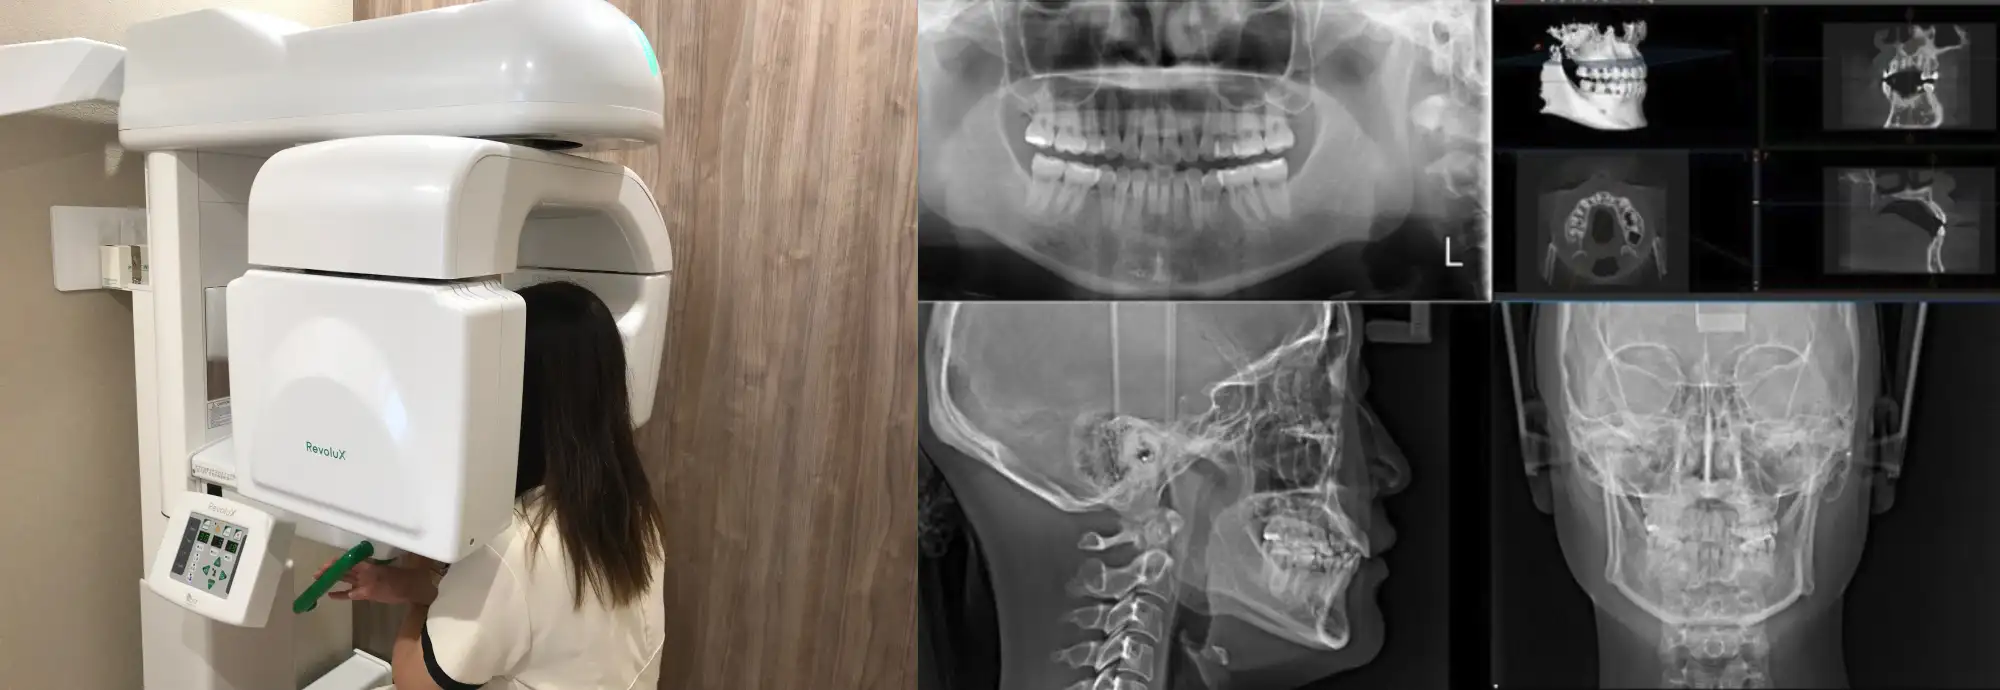

レントゲン

低被爆で安心してできるCTレントゲン

従来のレントゲンでは分かりづらかった、目には見えない骨の幅、量、歯根の長さを治療前に診断することで、より患者様に合った満足度の高い治療方針を導き出します。

当院では、治療を開始するすべての患者様にレントゲンCT画像診断を行っています。